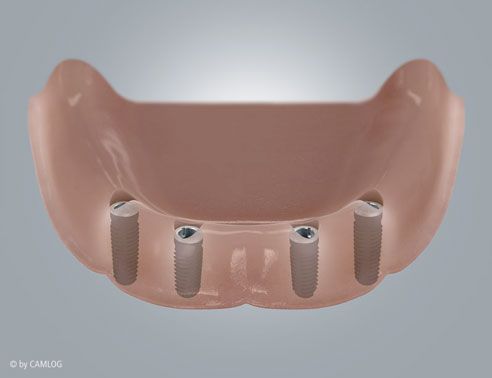

Tipp für Prothesenträger

Mit Hilfe von Mini-Implantaten können wir Vollprothesen im Ober- oder Unterkiefer fixieren. Wenn Sie sich maximalen Komfort im Alltag wünschen, sprechen Sie uns an. Wir beraten Sie gerne.